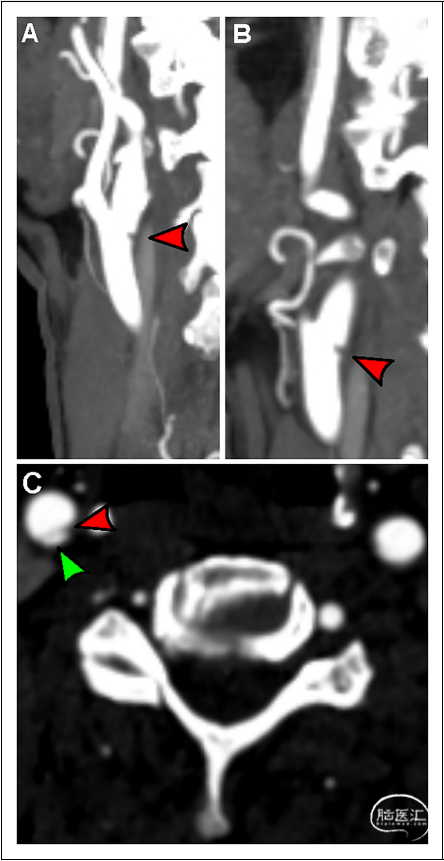

中心的所有形式的卒中在发病时都要经头颈部的CT血管成像(CTA)。因此,所有的颈动脉蹼首先都是在CTA上诊断出来的,并在CAS手术过程中通过导管血管造影得到证实。当矢状/斜位图像上颈动脉球后壁可见管腔板状充盈缺损区,轴位图像上可见薄膜状间隔(图1)时,即可诊断为颈动脉蹼。将同侧卒中归因于颈动脉蹼,必须满足ORF 10175急性卒中治疗试验(TOAST)阴性,并且具有潜在病因的患者不被归类为有症状的颈动脉蹼患者。因此,当满足以下三个标准时,患者被诊断为具有症状性颈动脉蹼:(1)相应血管区域的急性卒中或TIA;(2)CTA观察到的与颈动脉蹼一致的成像标准;(3)综合卒中检查未发现其他可能的卒中病因。

图1. 颈动脉蹼的计算机断层血管成像(CTA)。(A)斜位CTA,显示后颈动脉球部的充盈缺损(红色箭头)。(B)矢状位CTA再次显示充盈缺损区(红色箭头)。(C)轴位成像显示管腔充盈缺陷,有一细隔(红色箭头)将颈动脉蹼(绿色箭头)与颈动脉腔分开。